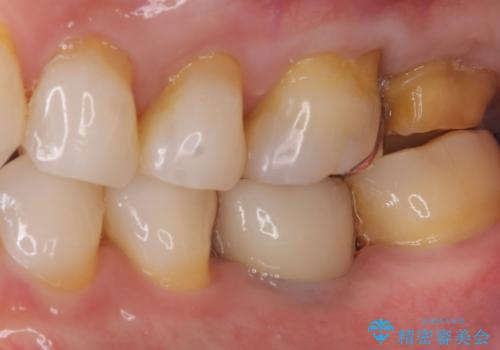

- 主訴:詰め物と歯の奥が側の境目に物がいつも溜まってしまう

保険適応のメタルインレーと歯質との間に不適合な箇所を認め、補綴物のやり替えでの治療となりました。インレーからクラウンへ補綴物の形態を変更し、素材は清掃性・適合性・審美性の点からセラミッククラウンでのやり替となりました。

レントゲン上にて、左上6番遠心にインレーと歯質の不適合を認めます。

健全歯質の残存量から、クラウンでのやり替えを提案しオールセラミッククラウン(スタンダード)でのやり替えとなりました。

・オールセラミッククラウン(スタンダード) 121,000円(税込み)

・仮歯 11,000円(税込み)